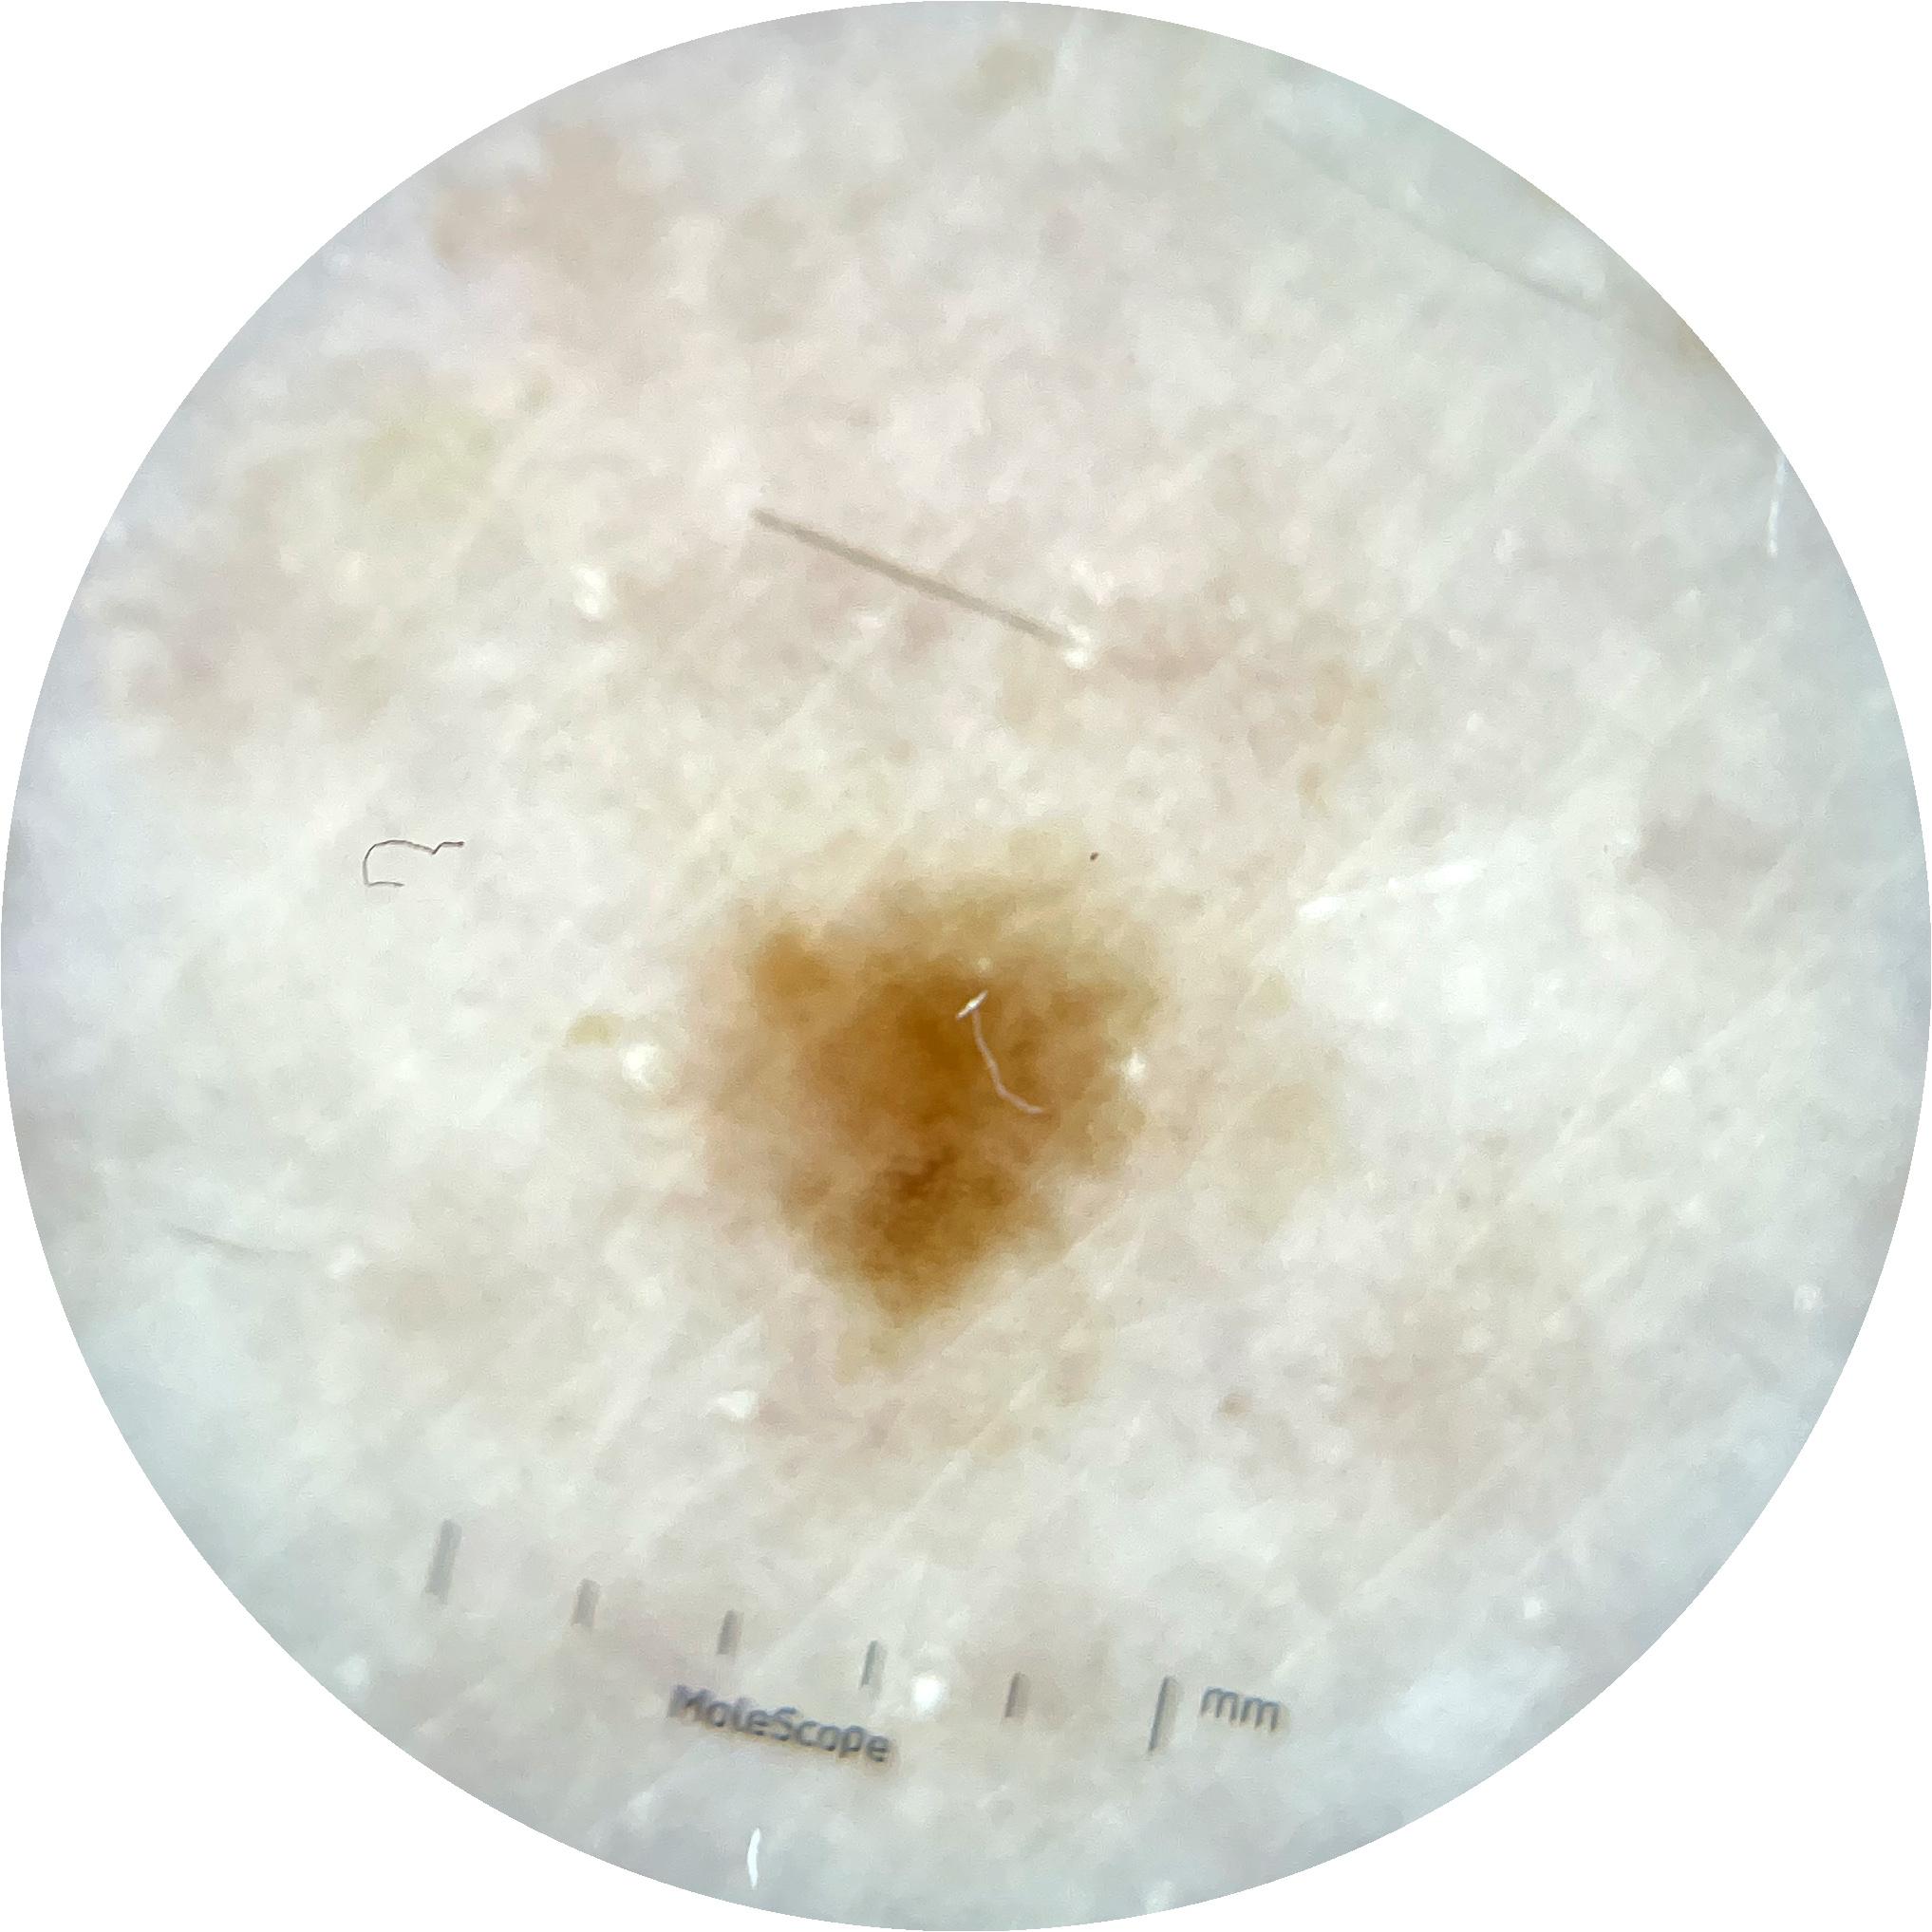

ISIC_9785574

image_type dermoscopic

lesion_id IL_0236417